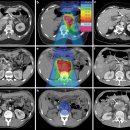

최첨단 방사선 암 치료 보고서! 중입자・양성자 치료로 암 정복을 향해 한 걸음 더 가까이 | KBS 240131 방송 2025.12.11해당카페글 미리보기

입자선 → 통합치료로 진화 결국 암은 점점 “치료 가능한 질환”으로 변모하고 있다. 14. 형의 ZPX(위상·파동) 관점에서 재해석 형의 이론과 의학물리학은 실제로 ‘위상·파동·공명’이라는 공통 구조가 있다. 브래그 피크 = 위상 에너지 집중(Δφ...